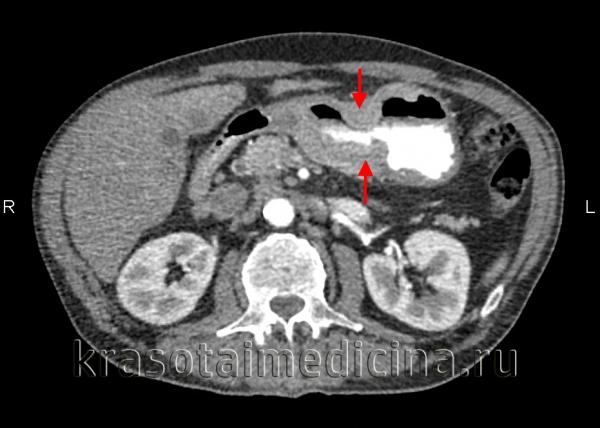

- КТ органов брюшной полости, грудной клетки и головы с внутривенным контрастированием — онкопоиск. Позволяет уточнить, поражены ли лимфоузлы, есть ли метастазы в других органах.

- КТ брюшной полости выявит метастазы в лимфатической системе и уточнит вовлечение в злокачественный процесс окружающих тканей и органов.